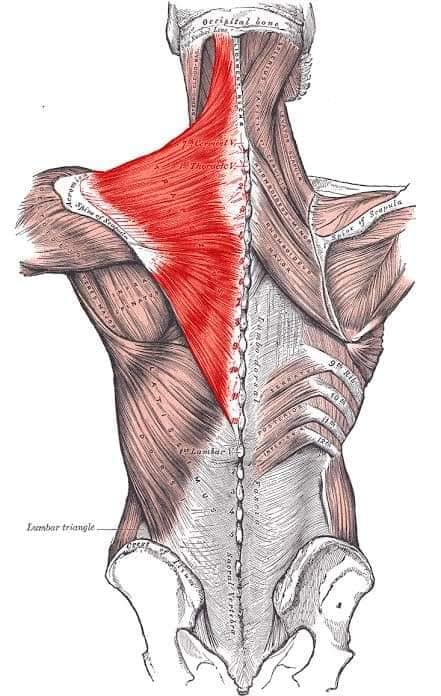

Поверхневі спинні м'язи

М'язи, що піднімають лопатку: Трапецієподібний м'яз: великий м'яз, що покриває верхню частину спини. Його функція - підтримка і рух лопаток, а також забезпечення стабільності хребта.

М'язи, що ведуть лопатку до хребта: Широкий м'яз спини: великий м'яз, що розташований в нижній частині спини. Він відповідає за рухи плечей і лопаток, а також за розширення верхньої частини тулуба.

Глибинні спинні м'язи

М'язи, що забезпечують стабільність хребта: М'язи, що розташовані між хребцями: включають мускулатуру, яка забезпечує стабільність і підтримку хребта, а також дозволяє здійснювати рухи хребта.